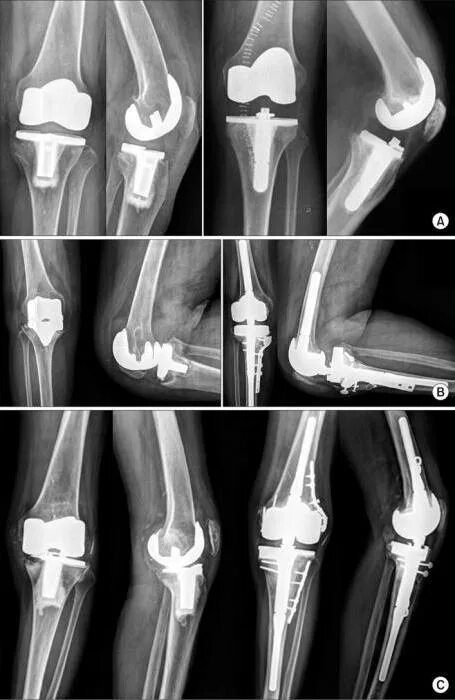

Протезирование суставов по квоте